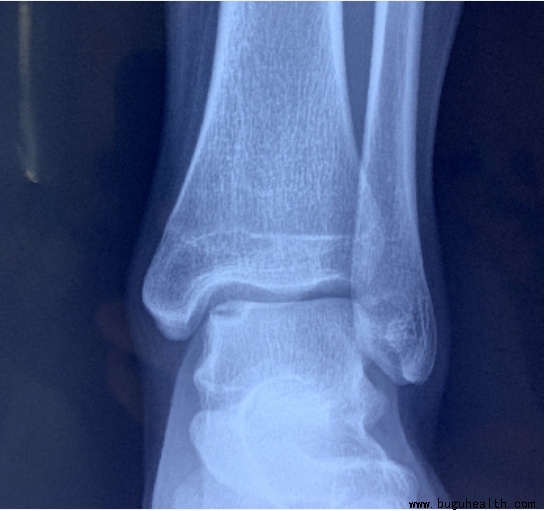

X光片上,我们只能看到踝关节的骨性的结构,这也是为什么有时候医生会要求再做核磁共振的检查来看看踝关节的周围,韧带、肌肉以及肌腱的情况。

踝关节扭伤病情严重的人,应到医院拍 X 片检查以排除骨折和脱位,明显移位的骨折或者脱位可能需要复位或手术治疗;